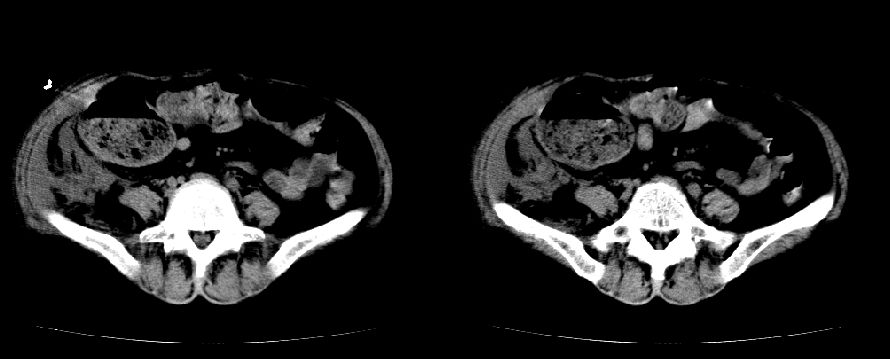

以下是引用liuyue在2008-7-19 10:17:00的发言:[br]考虑:1.肾周脓肿,肾实质、腰大肌及侧腹壁均受累及。 2.右肾囊肿。[br]建议:强化扫描,除外肾癌之可能。[br]

以下是引用zhengfaming在2008-7-19 14:48:00的发言:[br]右肾脓肿并感染可能性大,建议增强

以下是引用江广1996在2008-7-19 10:48:00的发言:[br]先考虑右侧肾周感染脓肿形成并累及腰大肌,右肾前侧有病灶考虑囊肿。